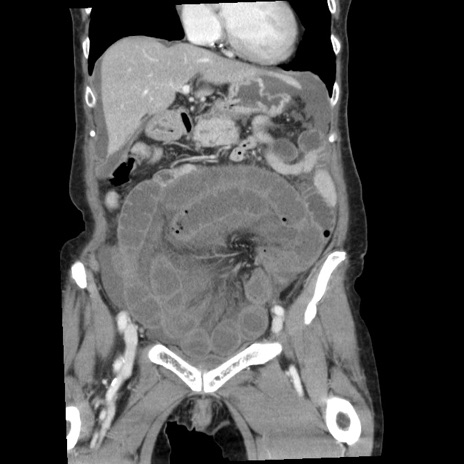

症例1(冠状断像)

【症例】80歳代女性

【主訴】腹痛

【現病歴】8時間前から腹痛あり来院。

【既往歴】糖尿病、脂質異常症、子宮体癌にて子宮全摘術

【身体所見】意識清明・会話良好だが腹痛で苦悶様、全腹部にわたって反跳痛と圧痛あり

【データ】WBC 13600、CRP 0.14、LDH 224、CK 90